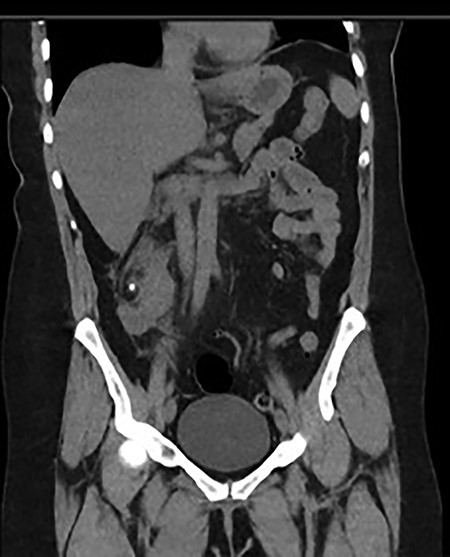

She was treated with ampicillin and a reduced dose of gentamicin given her AKI. Because of persisting shock, this patient was admitted to the intensive care unit (ICU) for inotropic support. Subsequently, both the urine and blood culture grew Escherichia coli. A repeat CT with contrast was performed due to persisting high fevers and severe right lower quadrant pain, which showed an early renal abscess (Fig. 2). Because of ongoing sepsis and absence of urology service in our hospital, the patient was transferred to another hospital where a urology service was available. She subsequently had insertion of a ureteric stent. The patient continued to improve post stent insertion and discharged when clinically well. She had removal of stone and ureteric stent 6 weeks later.

Progress CT showed worsening of perinephric inflammatory stranding and low-density area at the interpolar and upper pole of the right kidney representing an early renal abscess.